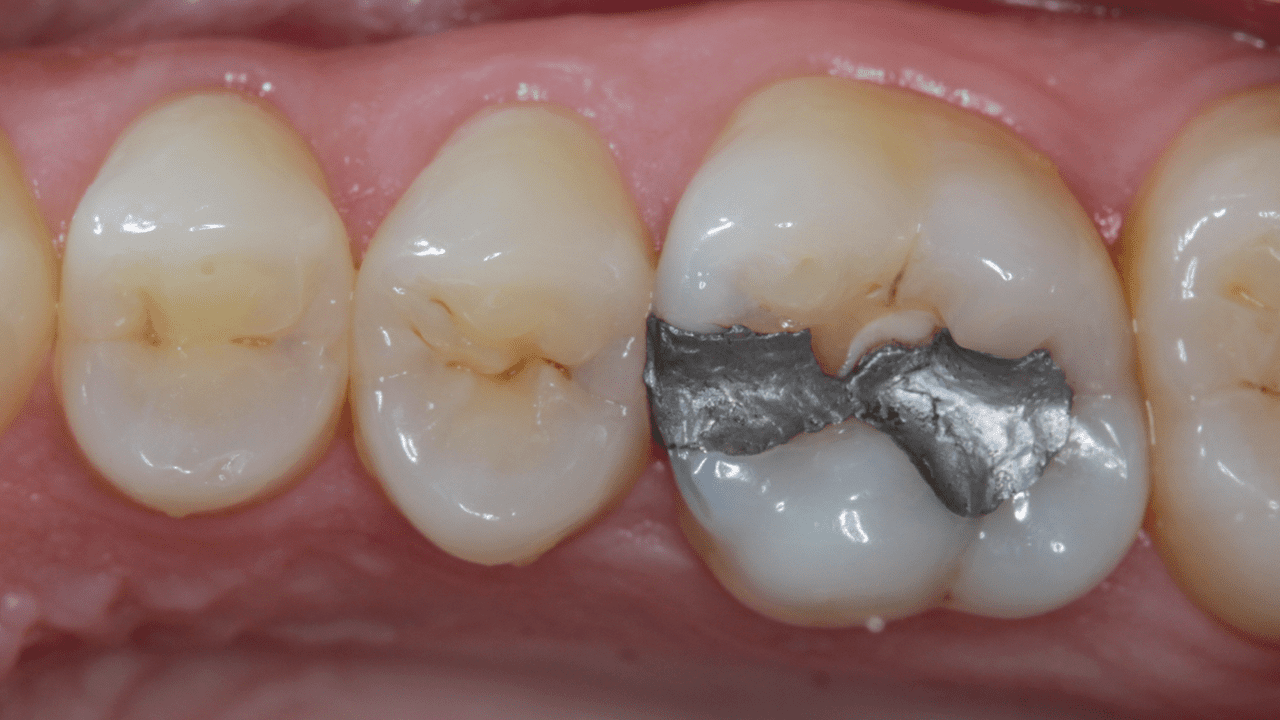

Багдад, Ирак

Случай: При первом осмотре была обнаружена неудачная (сломанная) реставрация амальгамой.

Результаты: повторный осмотр через 3 месяца. Окклюзионно-небная проекция, позволяющая увидеть превосходный блеск. Обратите внимание на характеристики и естественный внешний вид, которого удалось добиться при использовании универсального композита Neo Spectra ST (оттенки A2 и BW).